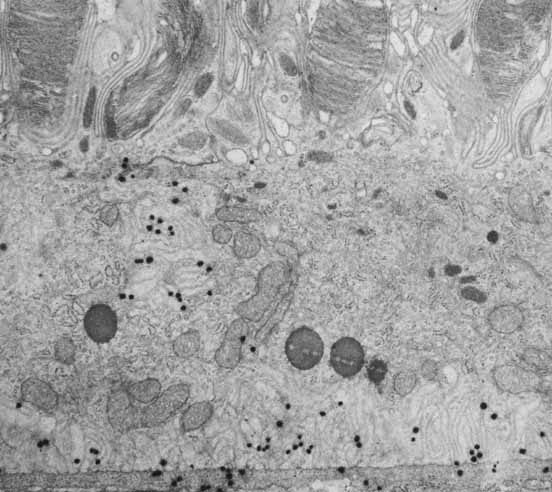

The histological appearance of the mature RPE proper (that associated with the NR) is of a simple cuboidal polarized epithelium.15 When viewed en face, as seen in an explanted intact sheet of RPE, the cells generally appear as tightly adherent cells with hexagonal packing. RPE cells possess a characteristic cytological appearance and organelle distribution (Fig. 4). In RPE cells, mitochondria are located basally, beneath the nucleus, and close to the basal infoldings of the plasma membrane. The cells contain numerous catalase-containing microperoxisomes that function in the conversion of hydrogen peroxide to water. The RPE cell cytoplasm contains mainly smooth, and relatively little rough, endoplasmic reticulum, a characteristic of cells actively involved in lipid metabolism.15 RPE cells possess a Golgi complex, an organelle in which newly synthesized molecules are sorted, modified, and targeted to appropriate sites in the cell, a function critical for maintenance of RPE cell polarity. The Golgi complex of RPE cells is small and often scarcely distinguishable from the other tubules and vesicles of the endoplasmic reticulum. Lipid droplets (homogeneous-appearing spheres 0.5 to 1 μm in diameter with no limiting membrane) are seen rarely in primate pigment epithelial cells but are common in amphibian and rat retinas, where they have been shown to be a normal site of vitamin A storage. There are approximately 5 million RPE cells in the human eye, and during development the density of pigment epithelial cells increases steadily in the macular area, gradually reaching a stable level 6 months after birth. In contrast, near the ora serrata, cell density starts at high levels and decreases rapidly through the first postnatal year and more gradually thereafter. Furthermore, there is some concomitant variation in the dimensions of RPE cells depending on the location in the eye, and further variation may occur with aging.16,17 In the macular region of the adult eye the cells are tall (14–16 μm) and narrow (10–14 μm), whereas toward the periphery they become significantly flatter and wider, such that at the ora serrata RPE cells may be 60-μm-wide (Fig. 5). After age 60, RPE cells throughout most of the retina become shorter, broader, and generally demonstrate a more variable morphology, with macular RPE cells increasing in height with advancing age. However, after age 90, when there has been cell loss, even macular RPE cells become wider and flatter. While these events represent generally slow responses to age-related intrinsic and extrinsic changes, RPE cells both in vitro and in vivo can exhibit rapid and wide-ranging phenotypic variation including epithelial-mesenchymal transformation and transdifferentiation.18,19 Such a capacity for plasticity may represent a necessary and beneficial ability to respond to disease and injury, and indeed differentiated mammalian RPE cells remain capable of cell division and wound healing.20 However, there is limited capacity for extensive repair, such as after damage of the deeper layers of Bruch's membrane, which often leads to scarring and lack of normal re-pigmentation.21 Furthermore, the normal program of RPE wound healing may be subverted by events such as exposure to vitreous and serum after rhegmatogenous retinal detachment, possibly resulting in the aberrant wound healing response and subsequent scarring seen in PVR.22,23 Thus, further elucidation of the molecular mechanisms underlying the phenotypic variability of RPE cells may provide important insights leading to therapeutic interventions in such circumstances.

Fig. 4 Electron micrograph of the retinal pigment epithelium in association with the outer segments of rods and cones. Retinal pigment epithelium (RPE) contains numerous elongated melanin granules that are aggregated in the apical portion of the cell, where the microvilli extend from the surface toward the outer segments of the rod and cone cells. The retina pigment epithelial cells contain numerous mitochondria and phagosomes. The arrow indicates the location of the junction complex between two adjacent cells, ×20,000. (Courtesy of Dr. Toichiro Kuwabara and reproduced from Ross et al. 2003)